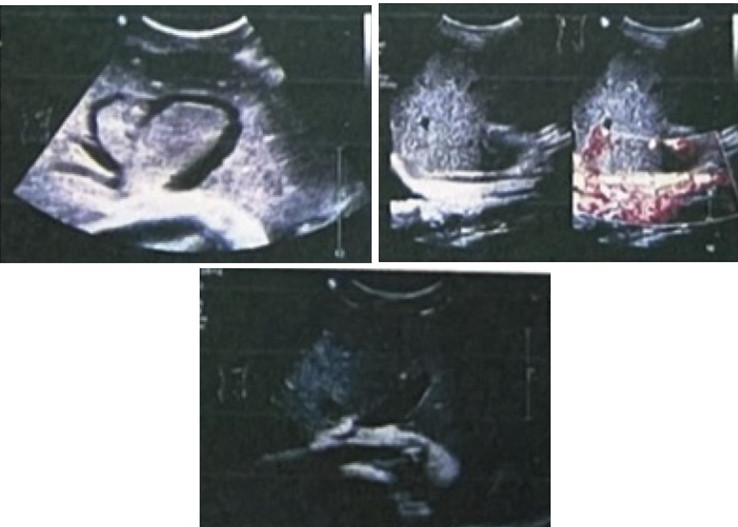

肝静脉、下腔静脉造影:中肝静脉显示,左肝、右肝静脉闭塞,下腔静脉全段充盈不良,显示不清(图3)。

图3  肝静脉和下腔静脉造影